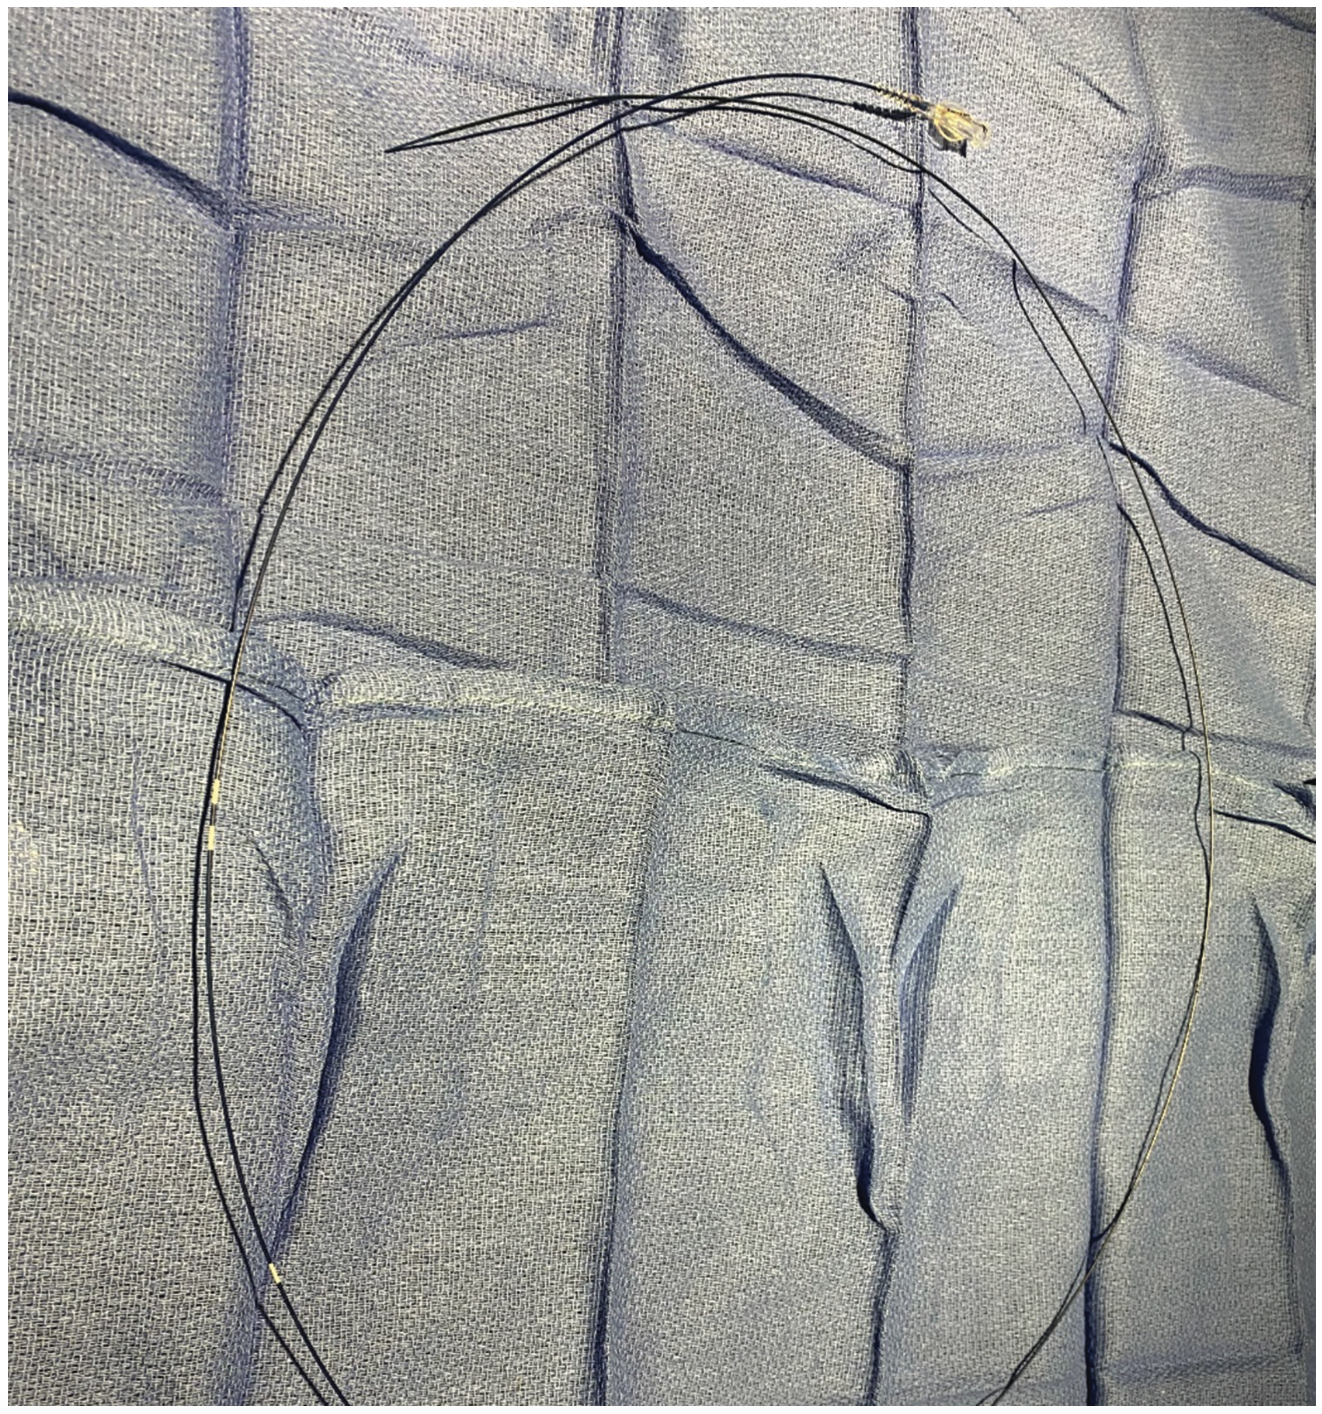

Femoral access was gained with a 6.0 Fr, 24 cm Arrow-Flex sheath (Telflex) (note longer sheaths can be used if desired). After routine coronary angiography, the aortic valve was crossed with a 5 Fr Judkin right 4.0 (JR4) catheter over a standard .014-inch J wire. Alternatively, to save a step, Amplatz left guiding catheters and moveable or fixed core straight wires can be directly placed in the LV. Simultaneous LV and aortic pressures were measured using the femoral long sheath pressure as a surrogate for the ascending aortic pressure, after verifying that aortic root and long sheath pressures were identical and superimposable, which is another technique useful for quickly measuring LV-aortic gradients. The use of this gradient as a surrogate for aortic root-to-LV gradients has been controversial; however, we find it to be suitable for most routine clinical decision making. Subsequently, the 5 Fr JR4 catheter was exchanged for a 6 Fr JR4 guide catheter over a standard .035-inch exchange-length J wire and the aortic valve was crossed with a JR4 guide catheter. An .014-inch Runthrough coronary wire (Terumo) was advanced into the LV. The guide catheter was pulled back into the ascending aorta, leaving the Runthrough in the LV. Next, a Twin-Pass microcatheter was advanced into the LV over the Runthrough wire. Simultaneous LV and aortic pressures were measured using the Twin-Pass and guide catheter. During pullback, premature ventricular contractions (PVCs) were induced when necessary with the Runthrough wire, and resting and provoked gradients were measured precisely, easily, and repetitively at various locations within the LV using LV-aortic pullbacks of the Twin-Pass over the guidewire. The pressure gradient, when measured by using the femoral sheath as a surrogate for the ascending aortic pressure and by directly measuring the ascending aortic pressure with the JR4 catheter, correlated well between the two techniques. The absence of a transvalvular pressure gradient and the presence of a LV outflow gradient with Brockenbrough-Braunwald-Morrow sign were evident, and these dynamic obstructive hemodynamics were easily measured and demonstrated with guidewire-provoked PVCs. Once measurements were complete, all catheters and wires were removed. Hemostasis was achieved with the use of an Angio-Seal (Terumo). Figures 1-5 show the instruments that were used and the waveforms that were obtained in this case.